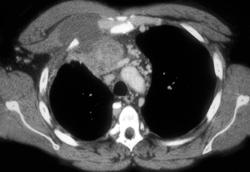

Thymoma